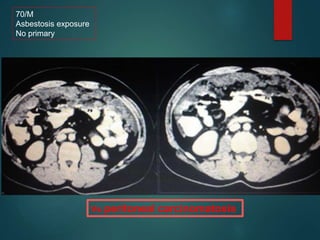

Malignant mesothelioma…

• Sheet like peritoneal thickening.

• Absence of lymphadenopathy

• Ascities is minimal

70/M

Asbestosis exposure

No primary

Vs peritoneal carcinomatosis

Malignant mesothelioma… • Justlike pleural mesothelioma ,it is associated with asbestosis exposure • Sheet like peritoneal thickening. • Absence of lymphadenopathy • Ascities is minimal

70/M Asbestosis exposure No primary Vsperitoneal carcinomatosis

• #49 Notice the sheet like peritoneal thickening. The diagnosis was suggested because of pleural calcification..

• #50 Here we see sheets of soft tissue density at ant abd wall.,omenthal thickening. The CT appearance of peritoneal mesothelioma may be indistinguishable from peritoneal carcinomatosis, lymphoma, and benign disease processes such as tuberculous peritonitis. The amount of ascites relative to the soft tissue component of mesothelioma may be disproportionately small as compared with peritoneal carcinomatosis in which ascites is usually a prominent feature